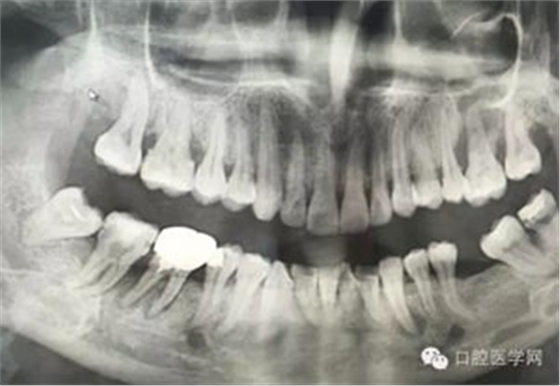

病例1:患者迫切希望保留自己的這一顆牙齒,根尖周陰影比較大,二度松動(dòng).而且旁邊有種植修復(fù)體,和患者溝通好后,治療好后觀察一個(gè)月后冠修復(fù),因?yàn)橛蟹N植的后期修復(fù),所以有了機(jī)會(huì)觀察,術(shù)后三個(gè)月和術(shù)后四個(gè)月,根尖恢復(fù)的還算不錯(cuò),希望能夠繼續(xù)觀察下去.這樣子的病例,做的時(shí)候我們一定要非常的小心,和患者要有充分的溝通以及不同科室的溝通然后決定怎么樣做比較好,假如就是出現(xiàn)了問(wèn)題,到時(shí)候我們也比較好處理些,免得我們自己到時(shí)候不好收?qǐng)觥?/span> 病例2:364647中齲的樹(shù)脂充填,現(xiàn)在樹(shù)脂的充填材料非常之多,有些時(shí)候,我們感覺(jué)有了好的材料我們就可以做出好的修復(fù),可是這是在我們有扎實(shí)的基本功的基礎(chǔ)上的,我們可以沒(méi)有那么好的樹(shù)脂,那么多的顏色選擇,修復(fù)的那么的逼真,但是我們至少要恢復(fù)患者牙齒的功能,將腐質(zhì)去除干凈,薄壁弱尖消除掉,選擇好適應(yīng)癥,給患者以盡可能好的修復(fù)。 來(lái)源于KQ88